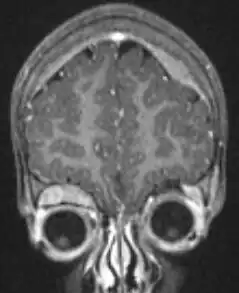

Microscopische opname van een typisch neuroblastoom met rosette formatie.

Onder de microscoop zijn de tumorcellen klein, rond en blauw, en vormen een rosettepatroon. Ook pseudorosetten zijn beschreven, waarbij de tumorcellen niet rond een bloedvat maar rondom een uitloper van een zenuwcel (een neutropil) zijn gegroepeerd. Het neuroblastoom is een van de perifere neuroblastische tumoren (pNT) en heeft eenzelfde soort oorsprong en heeft een breed patroon van differentiatie (uitgroeien tot een bepaald soort cel) variërend van goedaardig .ganglioneuroom via een stromarijk ganglioneuroblastoom met een mengsel van neuroblastoom-cellen in groepjes, tot een zeer kwaadaardig neuroblastoom. Dit onderscheid is samen met de leeftijd en de mitose-karyorhexis (kapot gaan van de celkern)-verhouding een belangrijk middel te bepalen of de vooruitzichten "gunstig " of "ongunstig " zijn. In 1999 is hier een indeling voor gemaakt, die in 2003 is herzien.[18]